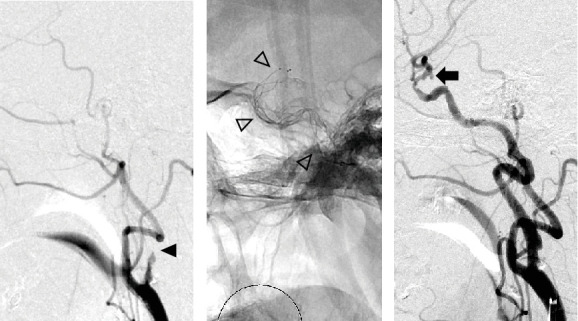

目的:随着机械取栓术(MT)在大血管闭塞性卒中中的应用越来越普遍,在MT靶血管中发现未破裂脑动脉瘤(uANs)的情况越来越多,需要通过病例积累来建立此类病例的MT安全指南。在这项研究中,我们的目的是回顾和报告我院与MT靶血管相关的uAN病例。方法:在2018年1月至2021年12月期间,我院320例大血管闭塞性卒中患者中,我们选择了在MT靶血管中有uAN的患者,并分析了各种参数,包括闭塞的血管、uAN位置、uAN发现时间、血栓取出程序、材料、再通结果和uAN破裂发生率。结果:320例患者中,7例发生靶血管动脉瘤(2.2%)。其中4例在器械穿过闭塞病变(病变交叉(LC))之前识别出病变,3例在LC或再通后识别出病变。在回顾性回顾中,3例中有1例在术前计算机断层扫描中怀疑有uAN。取栓程序包括1例患者单独直接抽吸首次通过技术(ADAPT), 2例患者单独支架置入术(SR), 3例患者联合治疗,1例患者SR联合尿激酶局部输注。有效再通率(定义为TICI 2b或3)为57.1%(4/7)。平均穿刺到再通时间为77.4分钟,没有一例与MT相关的uAN破裂。结论:我们报道了7例MT靶血管中的uAN。虽然我们采用了与常规MT相同的策略和技术,优先考虑再通,但没有uAN破裂与MT相关。术前图像评估更重要的是考虑到在MT靶血管中存在uAN的可能性,以及根据每个患者的情况仔细选择MT程序。

Objective: With the increasing prevalence of mechanical thrombectomy (MT) for large vessel occlusion strokes, encountering unruptured cerebral aneurysms (uANs) in MT target vessels has become more common, necessitating case accumulation to establish safety guidelines for MT in such cases. In this study, we aimed to review and present cases of uAN associated with MT target vessels at our hospital. Methods: Among 320 patients who underwent MT for large vessel occlusion strokes at our hospital between January 2018 and December 2021, we selected patients with uAN in the MT target vessel and analyzed various parameters including the occluded vessel, uAN location, timing of uAN discovery, thrombus retrieval procedures, materials, recanalization outcomes, and uAN rupture incidence. Results: Of the 320 patients, 7 had aneurysms in the target vessel (2.2%). The uANs were identified before the device crossed the occluded lesion (lesion crossing (LC)) in four cases, while in three cases, identification occurred after LC or recanalization. In 1 of the 3 cases, a uAN was suspected on preoperative computed tomography at the retrospective review. The thrombectomy procedures included a direct aspiration first pass technique (ADAPT) alone in one patient, stent retrieval (SR) alone in two patients, combination therapy in three patients, and SR combined with local infusion of urokinase in one patient. The effective recanalization rate, defined as TICI 2b or 3, was 57.1% (4/7). The average puncture-to-recanalization time was 77.4 min, and there were no instances of uAN rupture associated with MT. Conclusions: We presented seven cases of uAN in the MT target vessel. No uAN rupture was associated with MT, although the same strategies and techniques of routine MT at our hospital were employed, prioritizing recanalization. Preoperative image assessment considering the possibility of a uAN being present in the MT target vessel is more essential, as well as careful selection of MT procedures according to the situation of each patient.